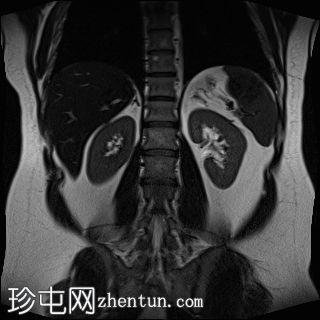

轴位T2加权像

脂肪抑制序列

T1低信号,T2低信号为主的脾脏肿块,内部可见T2高信号分隔,呈进行性强化。肿块中央可见星状瘢痕。

脾脏硬化性血管瘤样结节性转化(SANT),9.8 cm肿块

顾名思义,脾脏硬化性血管瘤样结节性转化(SANT)是一种纤维性血管病变。本病例展示了SANT的一些典型影像学特征,包括边界清晰的病灶,中央可见瘢痕,以及呈放射状进行性强化。这些特征使得术前MRI诊断较为明确。尽管SANT是一种良性病变,但大多数患者仍需行脾切除术以明确病理诊断。